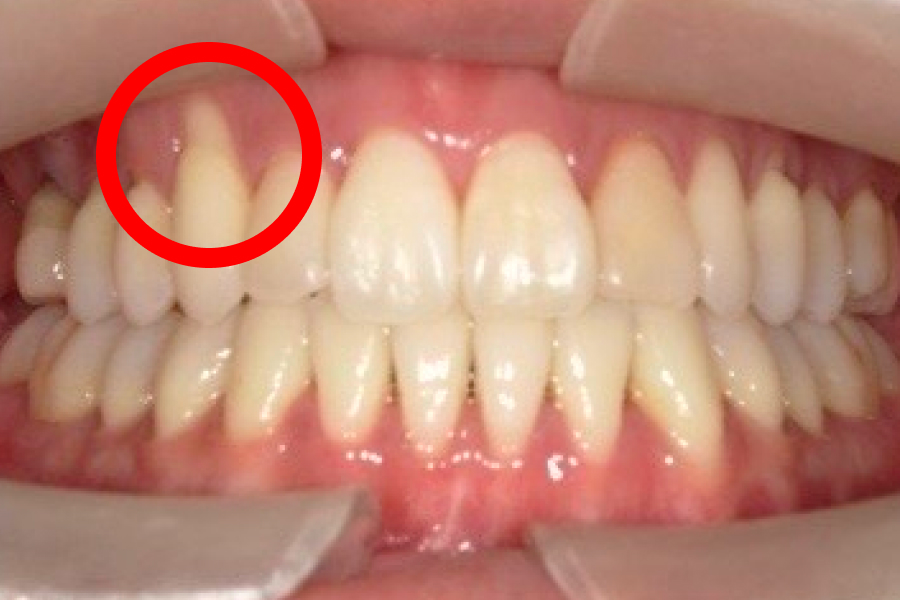

歯肉退縮が進むと、まず歯ぐきが下がって本来覆われていた根元が見えるため歯が長く見えるようになり、ついで歯根が露出することで冷水やブラッシングでしみる知覚過敏や根元のむし歯(歯根う蝕)、歯間が広がって食片が挟まりやすい・黒三角が目立つといった審美面の問題が生じます。

歯茎下がり症例

施術前

施術後